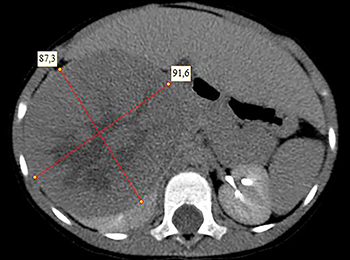

Рисунок 2. КТ: опухоль при поступлении.Клинически: при пальпации опухоль в проекции правой почки до 12 см в диаметре. Общеклинические исследования в пределах возрастной нормы. При КТ органов брюшной и грудной полости: КТ-картина объемного образования правой почки без признаков интрапульмональных метастазов (см. рис. 2). УЗИ брюшной полости: в проекции правой почки солидно-кистозное образование 101ґ114ґ99 мм, объемом 500 мл, васкуляризация активная, интактная часть почки 57ґ12ґ40 мм. Объемное образование правой почки — опухоль Вильмса. Предварительный диагноз: опухоль Вильмса правой почки, 2-я стадия.

Рисунок 3. Контрольная КТ: опухоль после предоперационной химиотерапии.Ребенку проведена предоперационная химиотерапия. На 5-й неделе лечения КТ-контроль показал уменьшение опухоли в размерах до 90ґ80ґ100 мм (см. рис. 3).